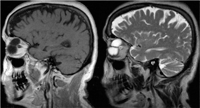

La resonancia magnética mostraba una lesión bien delimitada, homogénea e hipointesa en T1 e hiperintensa en T2, localizada en el cuadrante nasal superior y sin captación de contraste (

Figura 2 y

Tabla 1).

Figura 2. RMN (cortes sagitales). Izquierda: imagen de T1 que muestra una lesión de márgenes delimitados, homogénea e hipointensa que comprime el globo ocular desde su región superior. Derecha: imagen en T2 con la misma masa hiperintensa.